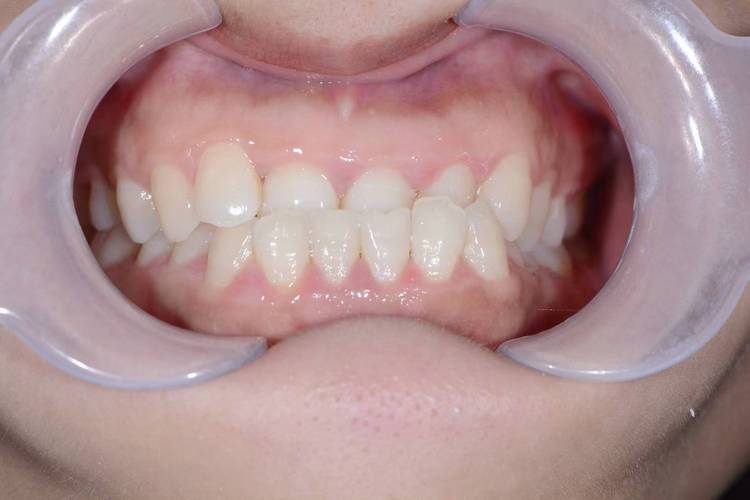

牙齿地包天,医学上称为反颌,是指下前牙咬合在上前牙的外侧,是一种常见的错颌畸形,这种咬合关系不仅影响面部美观,可能导致“月牙脸”“侧貌凹陷”等问题,还会降低咀嚼效率,长期甚至引发颞下颌关节紊乱、消化不良等健康问题,及时进行地包天矫正至关重要,而选择合适的矫正地方是矫正成功的第一步,地包天矫正的场所多样,不同机构各有特点,需结合自身需求综合选择。

- 技术与方案:根据病情选择合适技术,如儿童早期反颌可能需要功能性矫治器(如FR-III、 twin-block),成人骨性反颌可能需正畸-正颌联合治疗,隐形矫正则适合对美观要求高的患者。